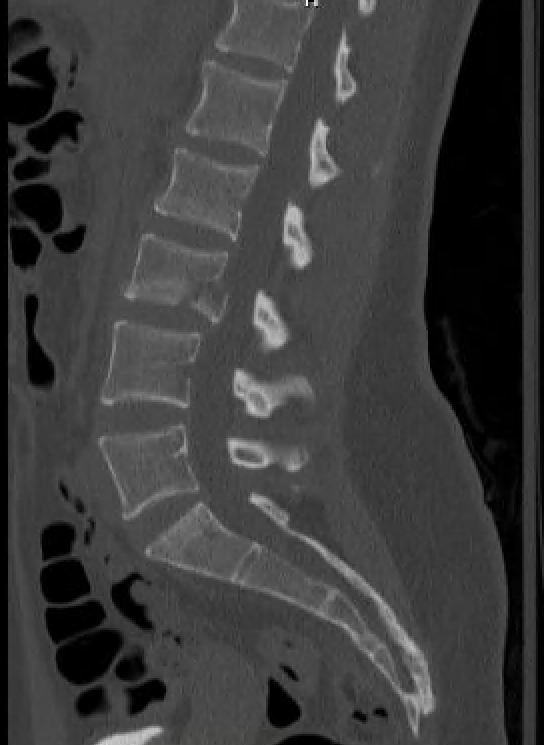

Skier Vs. Tree

A 19-year-old female presents to the ER via EMS after running into a tree while skiing. She says she swerved to avoid a fallen friend, skied off the trail, and hit a tree directly with her back. She has pain in her lumbar spine, but denies any numbness, tingling, or weakness. She says she cannot walk secondary to the pain. Her physical exam is notable for lumbar spine tenderness, with a normal distal neurovascular exam.

Read More...